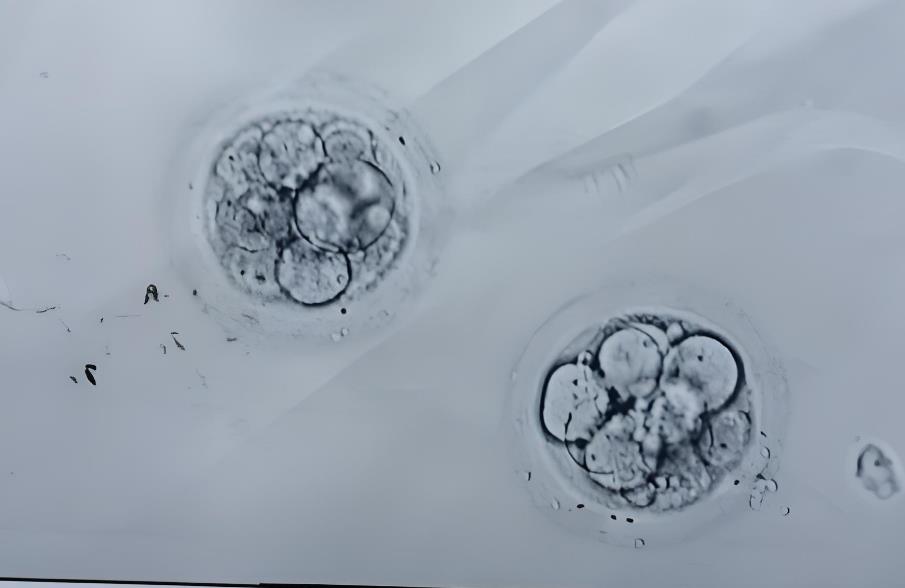

2024-10-11囊胚級別是評估胚胎質(zhì)量的重要指標之一。在試管嬰兒過程中,胚胎的質(zhì)量直接關(guān)系到著床成功率和未來胎兒的健康。那么,泰國試管嬰兒過程中看囊胚級別嗎?